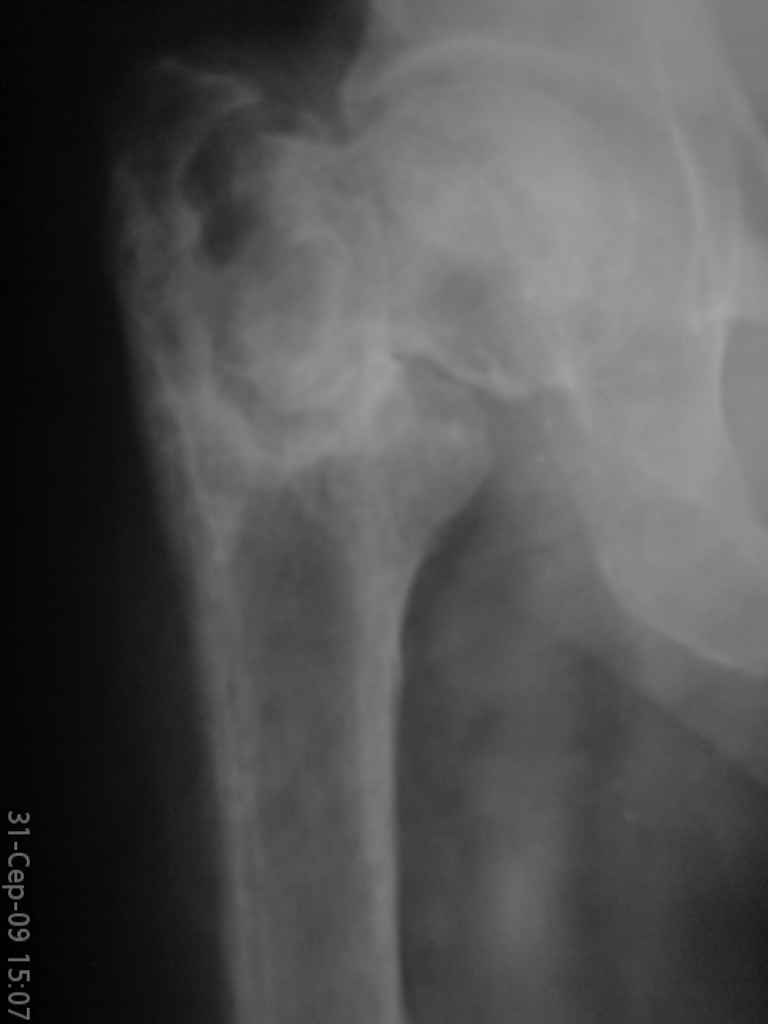

Уважаемые коллеги, помогите определиться с тактикой лечения. Больная, 62 года,жалуется на боли,неопорность левой ноги. Ходит с помощью костылей, укорочение ноги 3 см. Два года назад была оперирована кокой-то накостной пластиной, пластину удалили 4 мес назад. Вопрос такой: предлагать эндопротезирование или делать МОС (что-то по типу стержня Gamma)?За качество снимков извините, по данным МРТ - головка живая

На прошлой неделе оперировали похожего пациента. 2 года после неудачного остеосинтеза PFN в другом регионе. После удаления остатков железа выявилось несращение вертельной области.

В такой ситуации важно устранить варусную деформацию. При использовании гвоздя это непросто. Поэтому в число рассматриваемых

вариантов стоило бы включить вальгизирующую остеотомию с фиксацией 130-градусной клинковой пластиной или DHS.